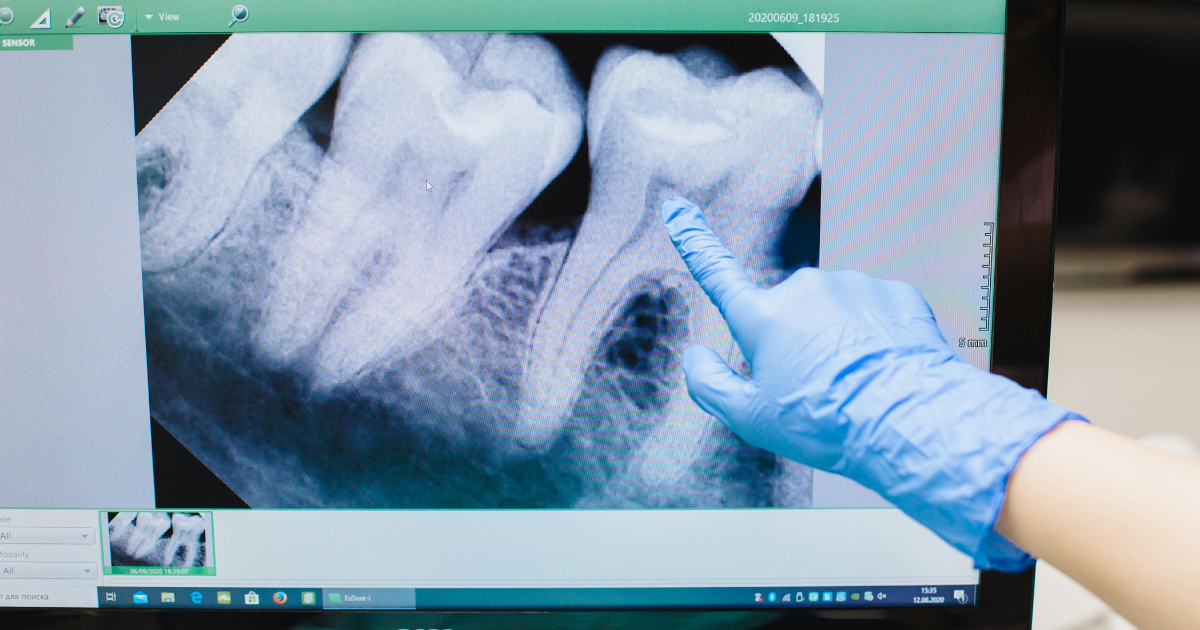

- incluso, cioè è intrappolato nell’osso mascellare o mandibolare. In questo scenario l’estrazione richiede un’ampia incisione gengivale, una rimozione significativa di tessuto osseo, un sezionamento sistematico del dente e dei punti di sutura.